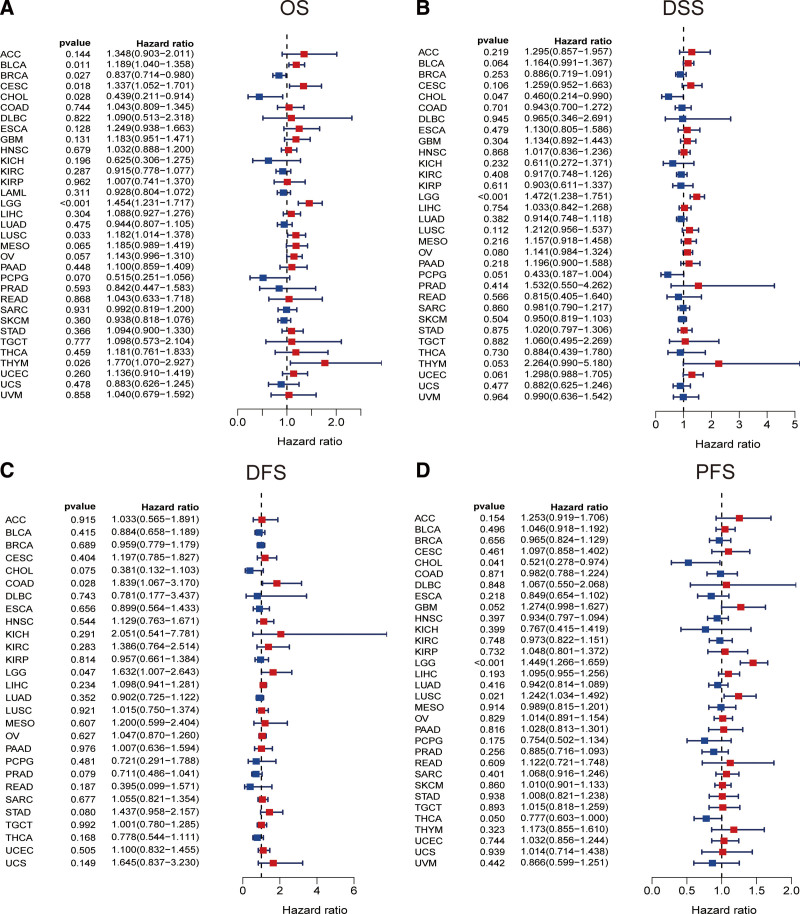

3.9. JUN prognostic value in pan-cancer

We then investigated the correlation of JUN expression and the prognosis of patients with various cancer types. Taking OS as observation outcome, we found significant correlation between JUN expression and OS of 7 cancers: BLCA, BRCA, CESC, CHOL, LGG, LUSC, and THYM. (Fig. 11A). Cox regression of DSS of patients also showed that JUN expression was significantly associated with DSS of patients with CHOL and LGG. (Fig. 11B). Cox regression analysis of DFS of OA patients indicated that JUN expression had non-negligible impact of the DFS of COAD and LGG (Fig. 11C). In terms of PFS analysis, a significant correlation between JUN expression and the PFS of patients with CHOL, LGG, and LUSC (Fig. 11D). This finding demonstrated that JUN was closely associated with multiple cancer types, especially in LGG.

To ascertain whether the obtained feature genes possess broader applicability, we combined our investigation with the current hotspot of immune infiltration. We extended these analyses to cancer, thereby enhancing the value of our research, and potentially broadening the applicability of these identified targets from OA to a more expansive context. By finding the intersection of immune genes obtained from InnateDB and Immport database and the 4 feature genes, we ultimately selected JUN to further explore its role in pan-cancer. We found that JUN were correlated with the clinical outcome (OS) of patients of BLCA, BRCA, CESC, CHOL, LGG, LUSC, and THYM. At the same time, we analyzed the TISIDB database and found a significant positively correlation between JUN expression level and lymphocytes, immunomodulators (including MHC molecule) and chemokines at pan-cancer level, especially in LGG. Therefore, above findings suggested that JUN had nonnegligible impact in shaping of the immune status in various cancers.